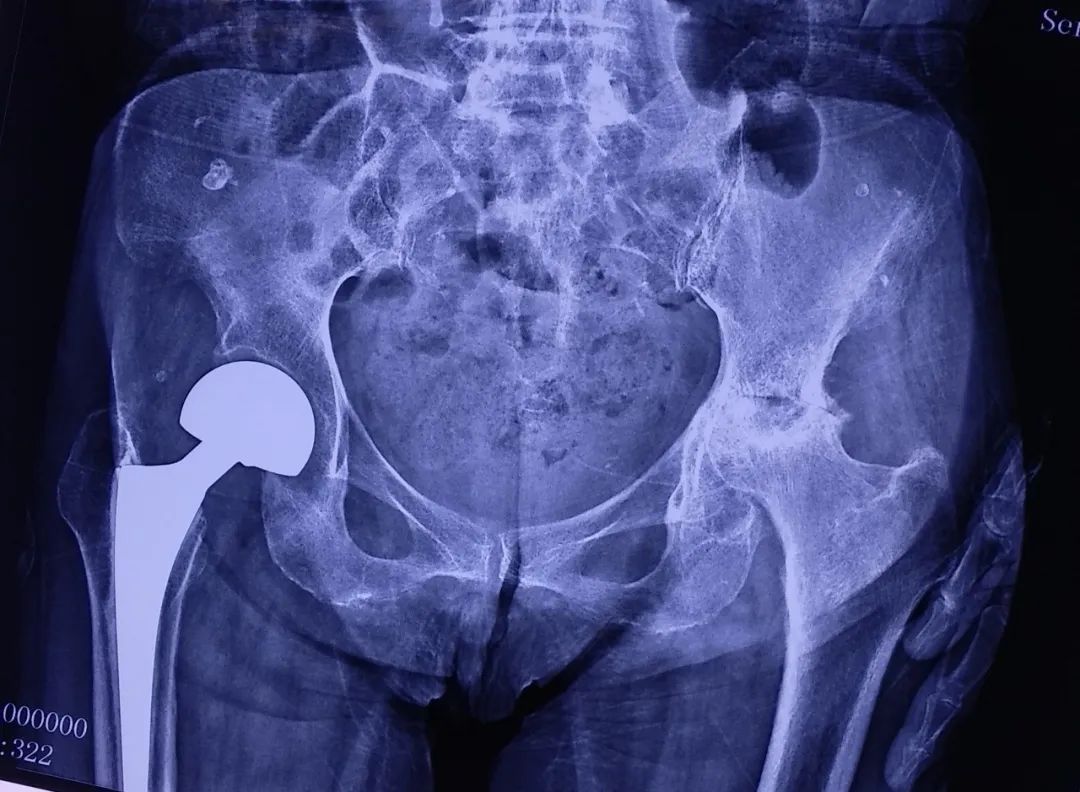

图:术前X线片

图:术前髋关节CT